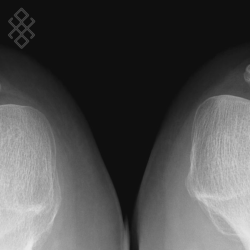

Radiographie du Genou